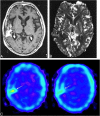

Background and purpose: Differentiation of tumor recurrence from treatment-related changes may be difficult with conventional MR imaging when newly enhancing lesions appear. Our aim was to determine the value of perfusion-sensitive contrast-enhanced MR imaging for differentiating recurrent neoplasm from nonneoplastic contrast-enhancing tissue.

Methods: Twenty patients in whom new enhancing lesions developed within irradiated regions were examined prospectively with perfusion-sensitive contrast-enhanced MR imaging. Twelve of them also underwent thallous chloride Tl 201 single-photon emission tomography (201Tl-SPECT). Normalized relative cerebral blood volume (rCBV) ratios and thallium indexes were evaluated to determine whether the new enhancing lesions were recurrent or not. Five instances of tumor recurrence and one of radiation necrosis were verified histologically; in the others, tumor recurrence was distinguished by lesions that progressively increased in size on serial MR examinations over at least 5 months, and nonneoplastic contrast-enhancing tissue was distinguished by lesions that disappeared or decreased in size on serial MR studies over at least 9 months.

Results: When normalized rCBV ratios were higher than 2.6 or lower than 0.6, enhancing lesions were either recurrent (n = 5) or nonneoplastic contrast-enhancing tissue (n = 3), respectively. All nonneoplastic contrast-enhancing tissue had a low thallium index, whereas three of four recurrent lesions had a high index.

Conclusion: An enhancing lesion with a normalized rCBV ratio higher than 2.6 or lower than 0.6 may suggest tumor recurrence or nonneoplastic contrast-enhancing tissue, respectively. In these cases, further examination with 201Tl-SPECT may not be necessary. However, when the normalized rCBV ratio is between 0.6 and 2.6, 201Tl-SPECT may be useful in making the differentiation.